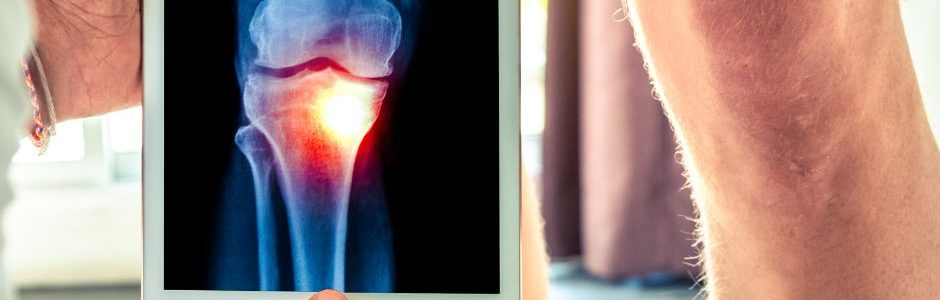

Knee pain can stop you in your tracks. Knowing when to seek knee pain relief in Arlington helps prevent further injury and speeds recovery. Urgent orthopedic care centers, like OrthoOIC, offer a practical solution for many knee injuries. What many patients don’t realize is that knee pain often signals an underlying issue. Those unaddressed issues worsen quietly if left untreated, even when discomfort feels manageable at first.

Falls, sports injuries, and overuse often lead patients to seek urgent care for knee injury concerns. Symptoms like swelling, instability, or difficulty bearing weight indicate the need for prompt evaluation. Early knee pain relief in Arlington supports better healing outcomes. Even minor twists or repetitive stress can disrupt the knee’s complex structure. Early diagnosis by an orthopedic specialist is helps patients avoid chronic pain or long-term instability.

Sudden pain, popping sounds, and visible swelling are generally signs of an acute injury to the knee, like ligament sprains, meniscus tears, or bone fractures. Swelling and lingering pain may also indicate inflammatory conditions that are often overlooked, like gout or bursitis. Instability or difficulty bearing weight are signs that your knee pain requires immediate attention. Quick action can mean the difference between a short recovery and months of limited movement, ongoing discomfort, or repeat injury.